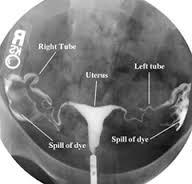

What is a hysterosalpingogram

Inject die into uterine cavity to assess shape of the cavity and patency of the fallopian tubes